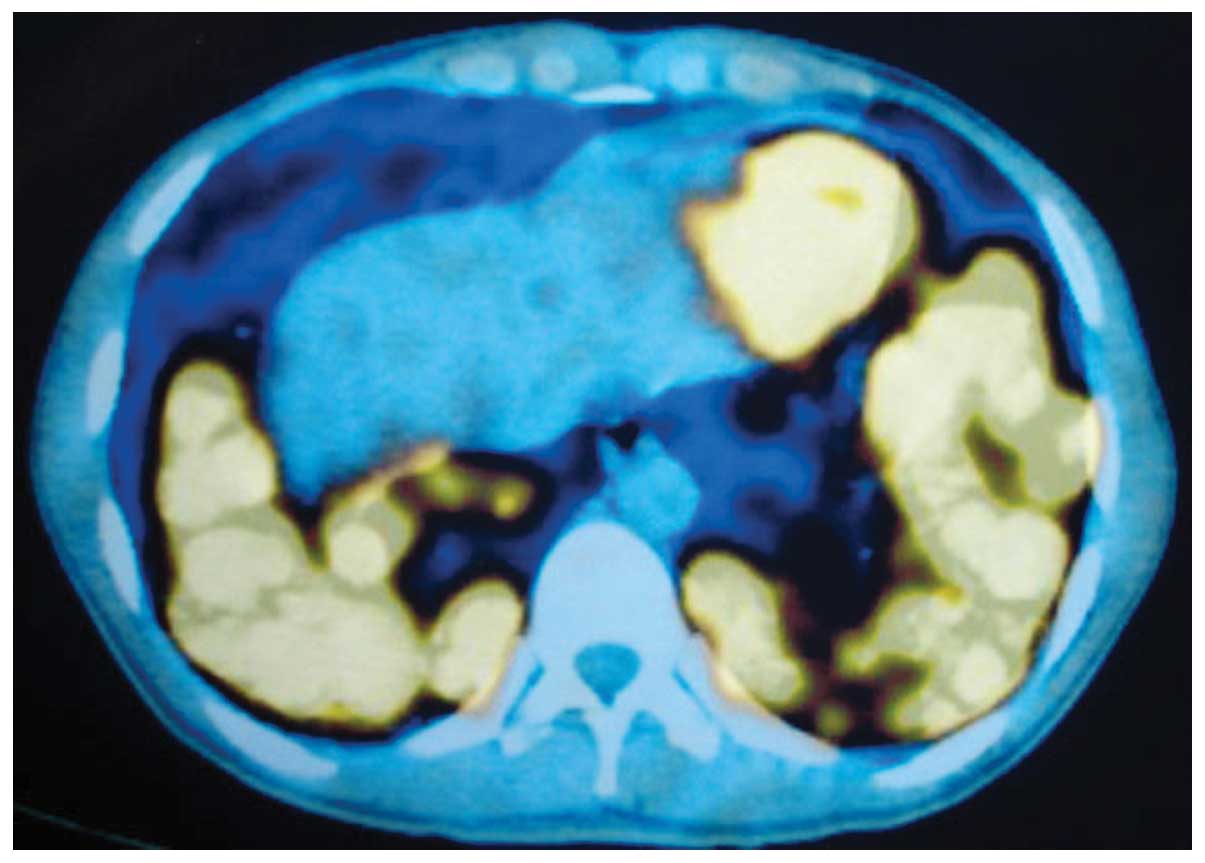

Lymphomatoid granulomatosis involving the central nervous system: A case report and review of the literature

Lymphomatoid granulomatosis (LYG) is a rare tumor with unknown etiology. Specific etiological factors for LYG are also unknown, although previous data indicates that LYG is an Epstein‑Barr virus‑associated B‑cell proliferation associated with an exuberant T‑cell reaction. According to the 2008 WHO classification, LYG is characterized by B‑cell proliferation of B‑lymphoma cells. Generally, treatment options for LYG are similar to those for diffuse large B‑cell lymphoma. Unfortunately, LYG is a chemotherapy‑resistant disease in certain patients and has a poor prognosis. The current study presents the case of a 19‑year‑old male patient with pulmonary LYG. The patient exhibited progressive disease following one cycle of chemotherapy with cyclophosphamide, adriamycin, vincristine and prednisone, and nodular lesions in the brain were diagnosed. Radiotherapy was delivered to the whole brain, however, this treatment did not prevent progression of the disease and the patient succumbed three months after initial presentation. An overview of the literature with regard to the etiology, clinical features, diagnosis and treatment options for LYG is also presented in the current case study.